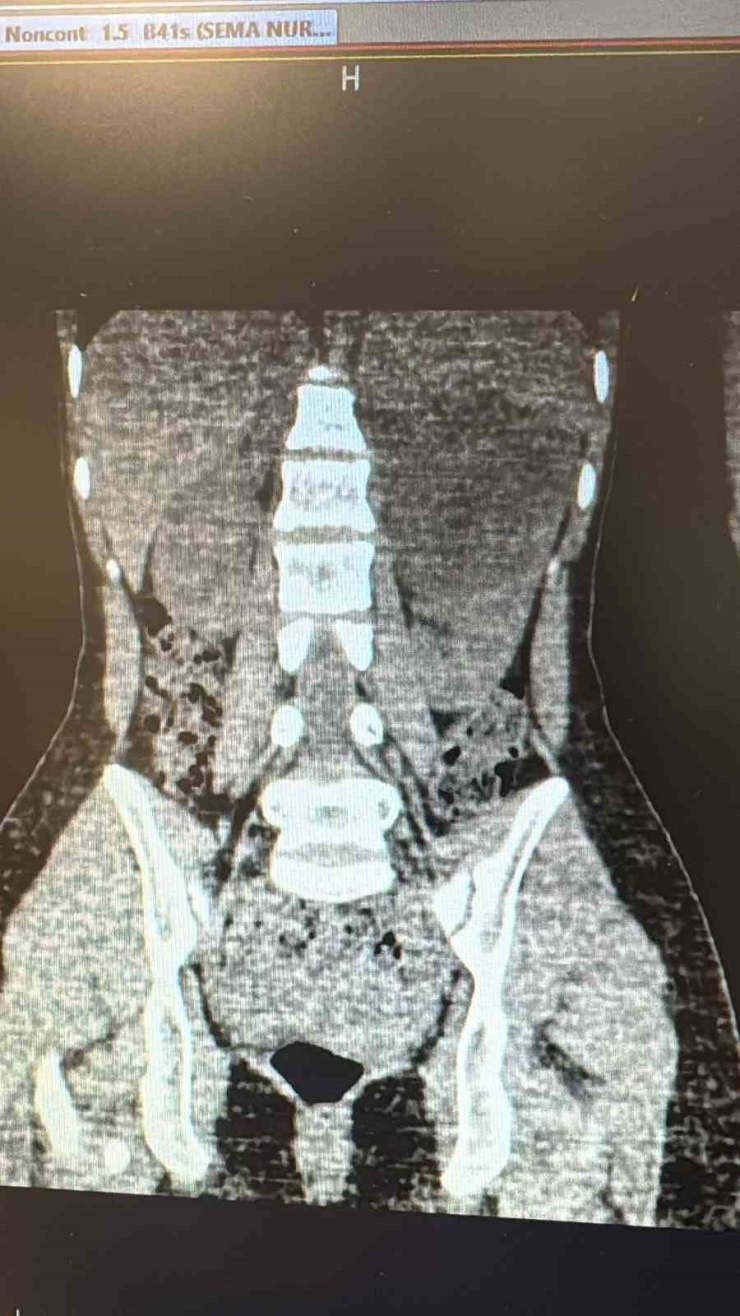

Uzun süredir sol yan ağrısı şikâyeti bulunan kadın hasta, dış merkezde yapılan tetkiklerde sol böbrekten kaynaklanan, böbrek ve dalağı iterek komşu organlara yapışıklık gösteren büyük bir kist tespit edilmesi üzerine Viranşehir Devlet Hastanesi'ne sevk edildi. Hastanede yapılan değerlendirmelerin ardından kistin cerrahi yöntemle alınmasına karar verildi. Üroloji kliniğinde gerçekleştirilen operasyonda, 10 santimetre boyutundaki böbrek kisti laparoskopik yöntemle, 2 adet 5 milimetre ve 1 adet 10 milimetrelik kesi kullanılarak çıkarıldı. Böylece hasta, açık cerrahiye gerek kalmadan tedavi edildi. Ameliyat sonrası takiplerinde herhangi bir komplikasyon gelişmeyen hasta, sağlığına kavuşarak taburcu edildi.